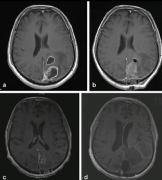

【脑干胶质瘤案例】手术辅助放化疗,较大脑干胶质母细胞瘤术后4年未复发,病史摘要:34岁男性,有6个月的左侧面部感觉丧失、听力障碍、轻度面瘫和右...